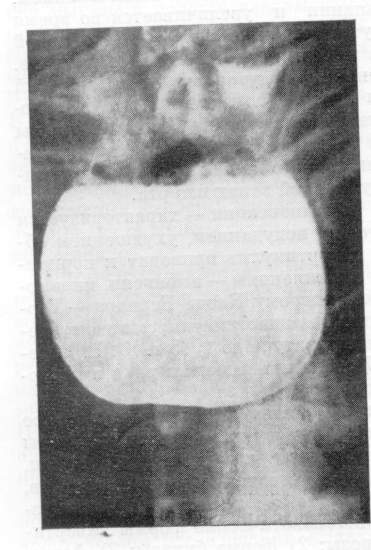

Дивертикулы диаметром до 2 см обычно не сопровождаются субъективными симптомами. Дивертикулы имеющие узкий вход или больше 2 см в диаметре, осложняясь дивертикулитом, проявляются периодическими болями за грудиной, в эпигастральной области, спине, дисфагией, срыгиваниями, какосмией, субфебрилитетом. А.Г.Земляной утверждает, что без боли нет дивертикулита (абсолютный признак).Рентгенологическое исследование позволяет достоверно выявить не только большие дивертикулы, но и маленькие, так как они имеют широкий вход и хорошо контрастируются (рис. 5, 6). Некоторые тракционные формы дивертикулов требуют контрастирования в горизонтальном положении тела. Задержка контраста более 2 минут в теле дивертикула со слоистостью содержимого свидетельствуют о развитии дивертикулита. Осложнения бифуркационных ДП редки и удовлетворительно переносятся больными, отчего прибегать к помощи хирургов практически не приходится. В литературе до 1968 г. опубликовано всего 148 операций по поводу осложненных форм бифуркационных дивертикулов. Обычно это были эрозивно-геморрагические эзофагиты, аспирационные пневмонии, бронхоэктазы, абсцессы легкого, эзофаго-бронхиальные свищи, медиастиниты, раковые перерождения.

Рис.5. Рентгенограмма. Тракционные эпибронхиальные дивертикулы.

Рис.6. Рентгенограмма. Большой бифуркационный дивертикул и дивертикулит.